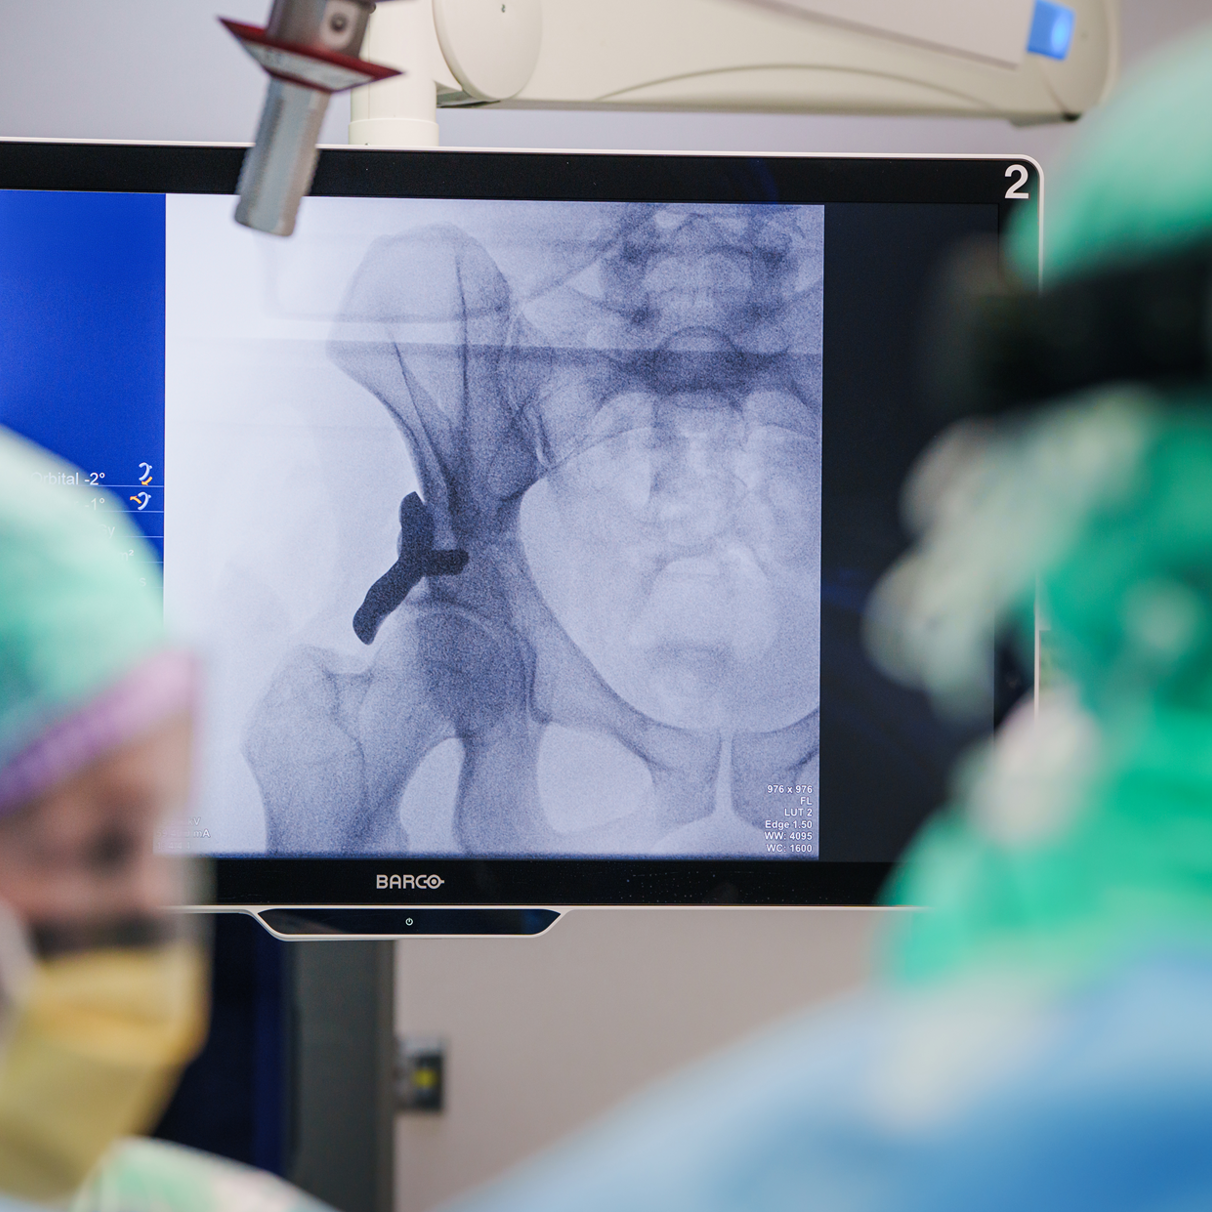

Voor het eerst ter wereld is vandaag een op maat gemaakt, 3D-geprint heupimplantaat bij een mens geplaatst. Orthopedisch chirurg en heupspecialist Rintje Agricola voerde de operatie uit in het Anna Ziekenhuis in Geldrop, in samenwerking met het Leids Universitair Medisch Centrum (LUMC). Deze innovatieve techniek, die eerder succesvol werd toegepast bij honden, kan op termijn een zware operatie bij patiënten met heupdysplasie voorkomen.

Deze ervaringen vormden de basis voor de vertaling naar mensen: een nieuwe behandeling met de zogeheten 3DHIP. In het Anna Ziekenhuis start nu een safety-trial, waarbij de nadruk ligt op veiligheid en technische uitvoerbaarheid. De eerste operaties worden uitgevoerd bij een kleine groep patiënten, waarbij de resultaten nauwgezet worden gevolgd.